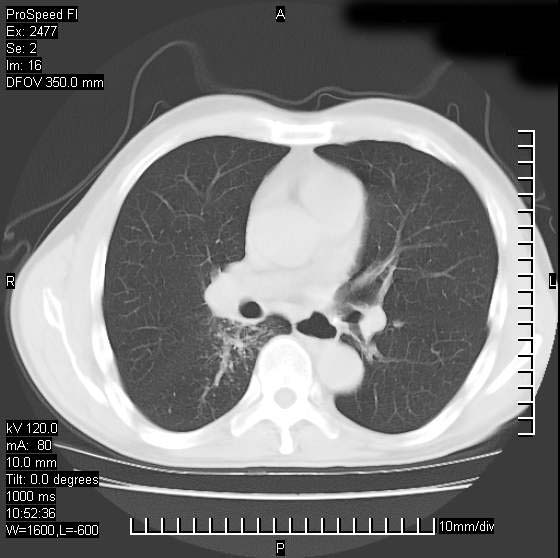

以下是引用天南地北在2007-10-9 14:29:00的发言:[br]1:右上肺结核[br]2:右肺下叶肿块:不支持肺癌,首先考虑炎性病变-肺脓疡可能性大[br]理由:1:临床病史支持,肺脓肿症状不明显应该是不规则服药造成。[br] 2:肿块边缘模糊,周围可见炎性渗出,长毛刺,内见支气管征,不过有点不规则。[br] 我感觉下肺癌这个诊断有点偏左,建议积极抗炎治疗后复查

以下是引用卜一在2007-10-9 15:55:00的发言:[br][br] [br] 1:右上肺结核[br]2:右肺下叶肿块:不支持肺癌,首先考虑炎性病变-肺脓疡可能性大[br]理由:1:临床病史支持,肺脓肿症状不明显应该是不规则服药造成。[br] 2:肿块边缘模糊,周围可见炎性渗出,长毛刺,内见空气支气管征,不过有点不规则。[br] 我感觉下肺癌这个诊断有点偏左,建议积极抗炎治疗后复查![br]支持! [br] [br] [br]

以下是引用wxy7406在2007-10-9 21:02:00的发言:[br]结合临床病史首先考虑感染性病变,但周围型肺癌不能除外,1.患者年龄偏大2.临床有咯血3.(也觉得是最重要的一点)病灶内有偏心性空洞。

以下是引用王仕学在2007-10-9 13:48:00的发言:[br]右下肺周围性肺癌可能性大,最好活检吧

以下是引用hhcckk在2007-10-9 15:18:00的发言:[br]右上肺病灶考虑结核,病灶多种形态并存(纤维化、增殖性病灶并存)[br]右下肺病灶比较难说,个人意见更趋向于“天南地北”的诊断----肺脓肿[br]1、病人有明显的寒战,高热,肿瘤病人很少出现[br]2、病灶周围的肺纹理走向柔和,没有肿瘤病灶常见的集束征[br]3、病灶边缘的毛刺较长,恶性肿瘤多为短毛刺[br]痰中血丝和病人的年龄是两个不利于良性肿块的因素,建议早点活检

以下是引用ydx_74在2007-10-9 15:53:00的发言:[br]右上肺结核,右下中心性肺癌可能大,肺门淋巴结肿大。